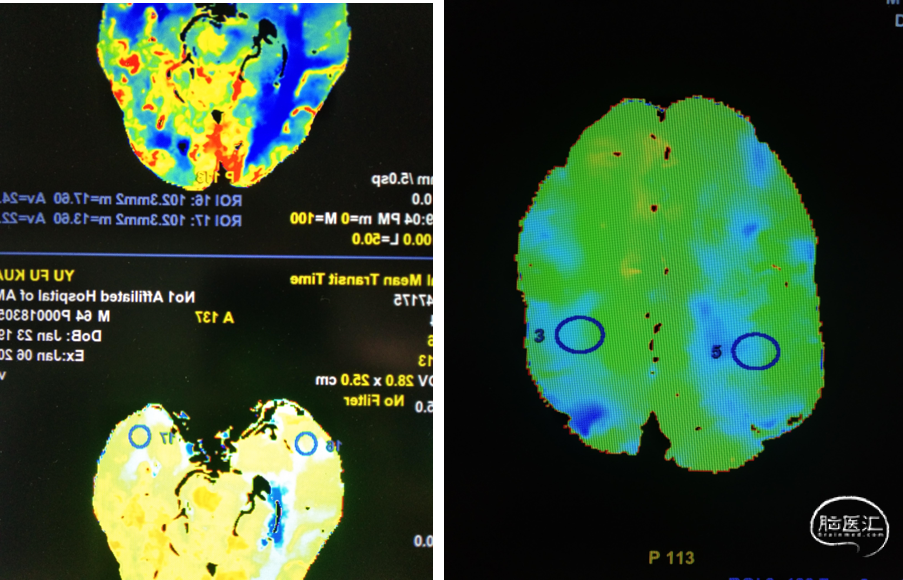

头颈部CTA

头CTP

重要影像结论:左侧颈内动脉慢性闭塞,右侧颈内动脉颅内段重度狭窄和右侧颈内动脉供血区低灌注。